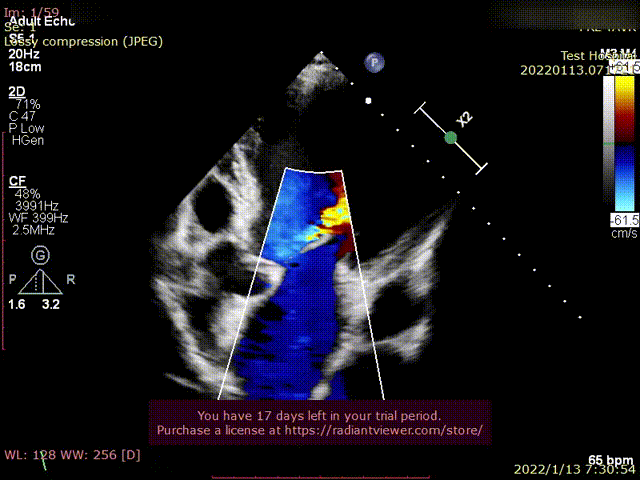

患者为68岁男性,因“胸闷、气促4余年,加重一年”主诉入院。术前超声心动图提示:左心增大,左室为著,左室壁肥厚,LVDD90 mm,LVEF35%,主动脉瓣右冠瓣脱垂、重度反流。术后即刻主动脉瓣大量反流消失,LVDD缩小至84 mm,左室较术前明显缩小。

术前超声影像

术后超声1

术后超声2